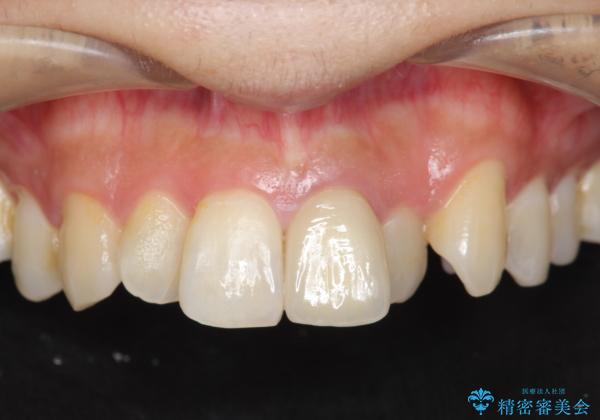

歯の変色 前歯の審美改善

- 前歯の変色の改善を求めて来院されました。

前歯は虫歯などにより神経治療がよく行われますが、経年的に変色が進み審美性が損なわれていきます。